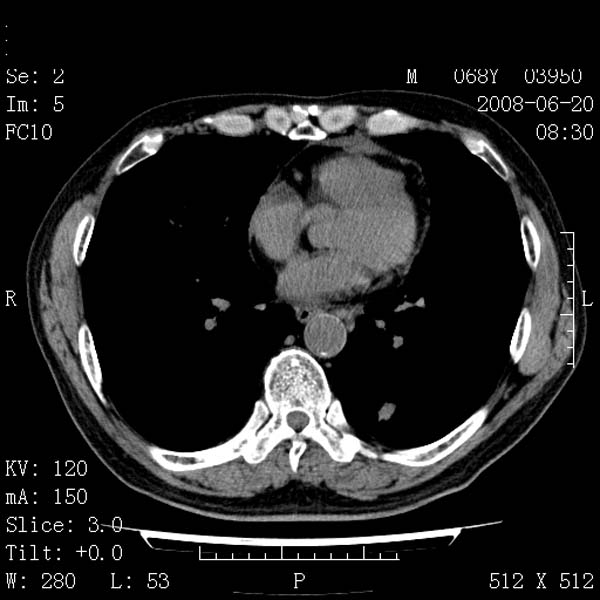

以下是引用守望可可西里在2008-6-24 1:11:00的发言:[br][br] 考虑为周围型肺癌:[br] 1.分叶结节,形态极不规则,蟹足样伸展的恶性浸润特征比较明确。[br] 2.磨玻璃影中由多个更高密度小结节聚集呈梅花瓣样。[br] 3.局部胸膜凹陷征比较明确。[br][br] 另:纵隔胸膜明显增厚、粘连。

以下是引用zjzjr在2008-6-24 11:19:00的发言:[br]支持左下肺周围型肺癌伴右肺转移,纵隔淋巴结转移,心包积液.

以下是引用zhangling在2008-6-24 14:56:00的发言:[br]我们科室意见报告为[br][br]1考虑左下肺周围型肺癌[br]2右肺小结节考虑转移瘤,纵隔淋巴结转移[br]3心包积液. [br] 各位老师分析的相当好 谢意[br]